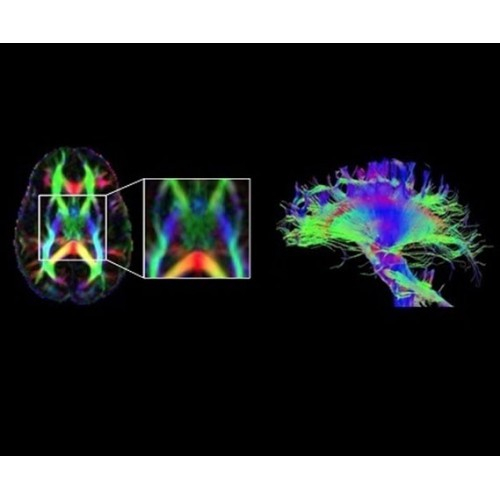

Компания GE Healthcare представляет революционную, полностью интегрированную систему SIGNA PET/MR1, в которой сочетаются времяпролетная технология (TOF) и возможности напряженности магнитного поля 3.0 Тл. Мы поможем вам поднять исследования на более высокий уровень. SIGNA PET/MR позволяет достичь впечатляющей точности и скорости исследований, а благодаря новейшей технологии реконструкции Q.Clear2 качество изображений улучшается в два раза. Кроме того, в систему включен полный набор клинических приложений и гибких катушек для проведения любых видов исследования, открывая для вас возможности визуализации, о которых вы даже не догадывались.

В систему SIGNA PET/MR встроены запатентованные детекторы кремниевого фотоумножителя (SiPM) и сверхчувствительные кристаллические сцинтилляторы на основе лютеция толщиной 25 мм. Благодаря этому обеспечивается исключительная чувствительность и возможность использования времяпролетной диагностики (TOF).

Кроме того, в результате использования технологии TOF и инновационной технологии реконструкции Q.Clear вы сможете добиться прекрасного соотношения сигнал/шум. А благодаря технологии нулевого времени эхо (ZTE) визуализировать костную структуру без ионизирующего излучения. Все эти разработки для улучшения качества сканирования и точности анализа помогут вам использовать весь потенциал ПЭТ/МРТ.

Новейшая платформа SIGNA Works4 повышает производительность ключевых технологий визуализации GE Healthcare. SIGNA Architect поставляется с предустановленными стандартными приложениями. Расширенные функции SIGNA Works с возможностью обновления позволят устанавливать новые приложения в соответствии с растущими потребностями вашей клинической практики.

Стандартный пакет приложений SIGNA Works позволит вам достичь желаемых результатов в клинической практике благодаря набору высокоэффективных средств визуализации. Программные приложения, входящие в состав данных клинических пакетов, включают широкий спектр контрастов, функции обработки 2D- и 3D-данных, а также возможность коррекции артефактов движения. SIGNA Works предоставляет набор инструментов, необходимых для проведения эффективного клинического исследования.